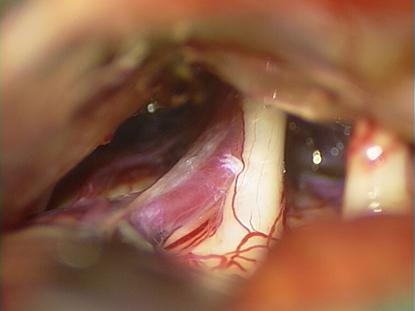

Mobilisierung der Gefäßschlinge vom Nerven

Beginn der Positionierung von Teflon

Vollständige mikrovaskuläre Dekompression des Nerven. Eine erneute Kontaktbildung ist nicht mehr möglich.